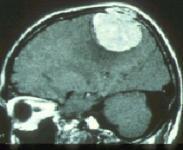

腦膜瘤癥狀

• 腦膜瘤

628健康網為您分享有關腦膜瘤的癥狀,腦膜瘤的治療方法,腦膜瘤的預防知識,腦膜瘤的癥狀圖片,腦膜瘤吃什么藥,腦膜瘤怎么治...